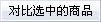

AM5101861 č└ė├õS č└ų▄ 1# ų▒ ░╦ĮŪ▒·

AM5101862 č└ė├õS č└ų▄ 2# ėęÅØ ░╦ĮŪ▒·

AM5101863 č└ė├õS č└╣Ū 1# ╝ŌłA/╝ŌłA ▒Ō▒·

AM5101864 č└ė├õS č└╣Ū 2# ķLłA/╝ŌłA ▒Ō▒·

AM5101865 č└╣ŪÕN 18cm ╦▄▒·

AM5101866 č└╣ŪÕN 15cm Įī┘▒·